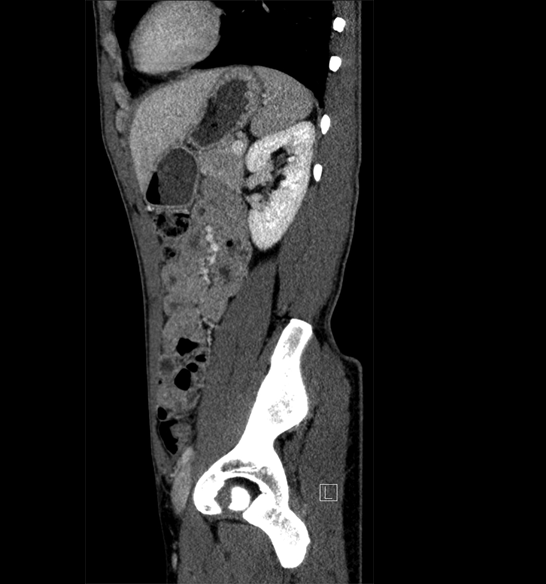

Body

Covers abdominal CT anatomy.